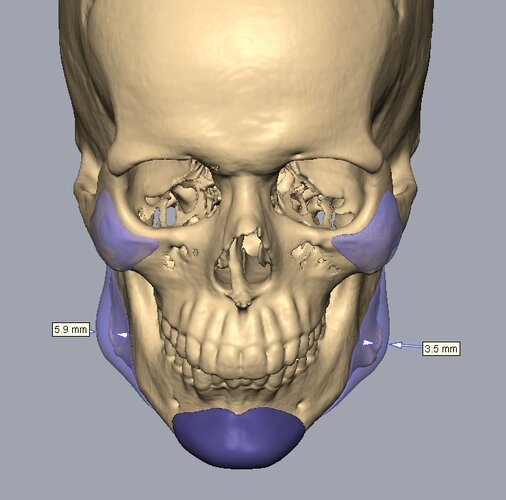

Recieved the draft 1 of the design, what changes should i ask for?? a couple of things i can think of are malar implants not giving enough lateral protrusion, gonion flaring.

I also am planning to include infra implants as well.